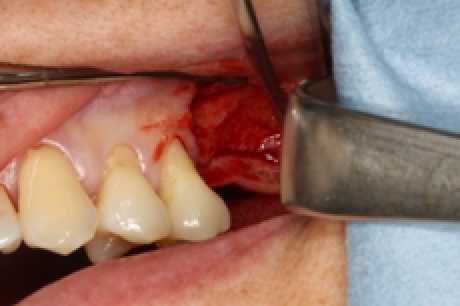

骨再生療法後。手術より6ヶ月後の状態です。

予定通り、インプラントを埋入しました。使用インプラントはプラトンタイプ4です。